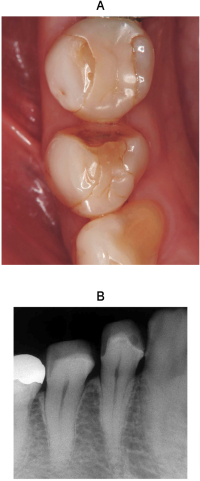

50歳の女性。下顎右側第一小臼歯修復物の破折を主訴として来院した。2日前に硬いものを嚙んだときに破折したという。エアーで一過性の疼痛を認める。患者は同じ材料での修復を希望している。間接修復を行うこととした。初診時の口腔内写真とエックス線写真を別に示す。

窩洞形成で留意すべきなのはどれか。1つ選べ。